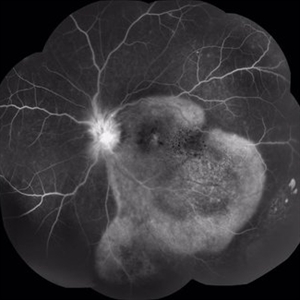

66-year-old woman with acute visual acuity loss.

Photographer: Claudio Zett Lobo, UNIFESP

Imaging device: Intravenous Fluorescein angiography

Condition/keywords: acute syphilitic posterior placoid chorioretinitis